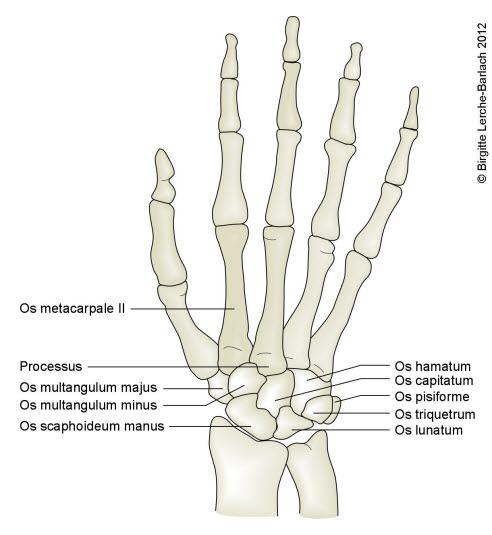

Underarmen består av to bein, spolebeinet (radius) på tommelsiden og albuebeinet (ulna) på lillefingersiden. Disse to beina holdes fast sammen av bindevev (syndesmose). Beina danner albueleddet sammen med overarmsbeinet (humerus), og håndleddet sammen med håndrotsbeina.

Brudd i nedre del av radius, mindre enn 4 cm fra nedre ende av beinet, betegnes på fagspråket som distalt radiusbrudd eller fractura radii typica. Denne bruddtypen kan medføre at de to bruddendene spriker eller blir forskjøvet i forhold til hverandre, men bruddet kan også være uten forskyvning av bruddendene. I unntakstilfelle kan bruddet skade nerver som ligger nær.

Brudd i håndleddet er den vanligste bruddskaden som forekommer. Bruddtypen er hyppigst hos eldre kvinner, men det er heller ikke uvanlig hos yngre personer. Cirka 90 prosent av bruddene innebærer at det ytterste bruddstykket er skjøvet opp (dorsalt, mot håndryggssiden) - denne bruddtypen kalles også Colles brudd (se tegningen over).

Selv om vi bruker betegnelsen håndleddsbrudd, så er det ikke et brudd i selve håndleddet, men noen få centimeter ovenfor leddet.